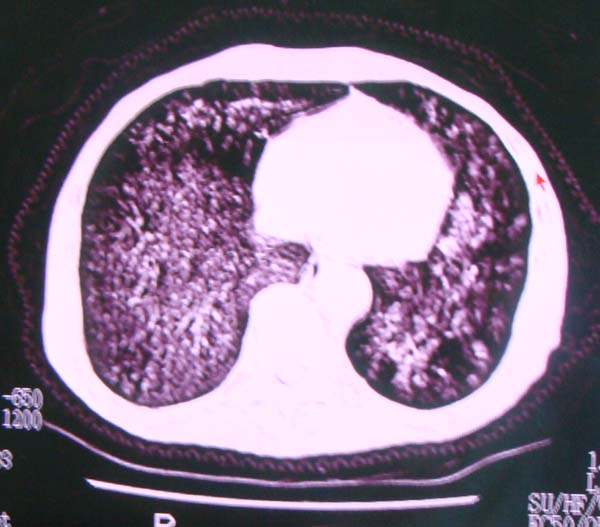

以下是引用zhangzhongshou在2008-2-15 22:25:00的发言:[br]片子照得不清,基本考虑1、细支气管肺泡癌2、亚急性血行播散型肺结核。请结合临床。片子细节显示不清,无法提供进一步意见。

以下是引用杀毒软件在2008-2-15 22:34:00的发言:[br]小叶中心性肺气肿。两肺弥漫性病变,肺泡微石病,过敏性肺炎,尘肺2期,特发性肺纤维化都有可能。[br]不象肺泡癌。